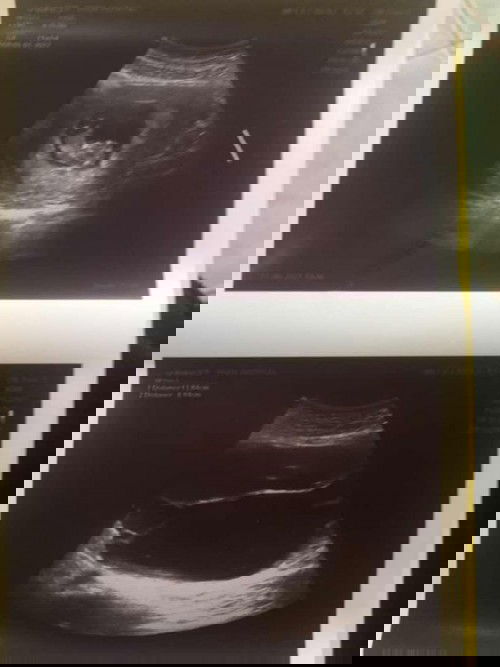

เป็นซีสต์ระหว่างตั้งครรภ์

ใครมีประสบการณ์เป็นซีสต์ระหว่างตั้งครรภ์บ้างค่ะ หมอบอกว่ามีขนาดใหญ่ 13 เซน ยังไม่ให้ผ่า ต้องรอดูว่าจะใหญ่ขึ้นอีกไหมถ้าเริ่มเบียดลูก ก็จะผ่า แล้วถ้าผ่าเอาซีสต์ออกจะเป็นอันตรายต่อลูกไหมค่ะ#ท้องแรกคะ #ใครมีประสบการณ์ #ขอบคุณล่วงหน้านะคะ